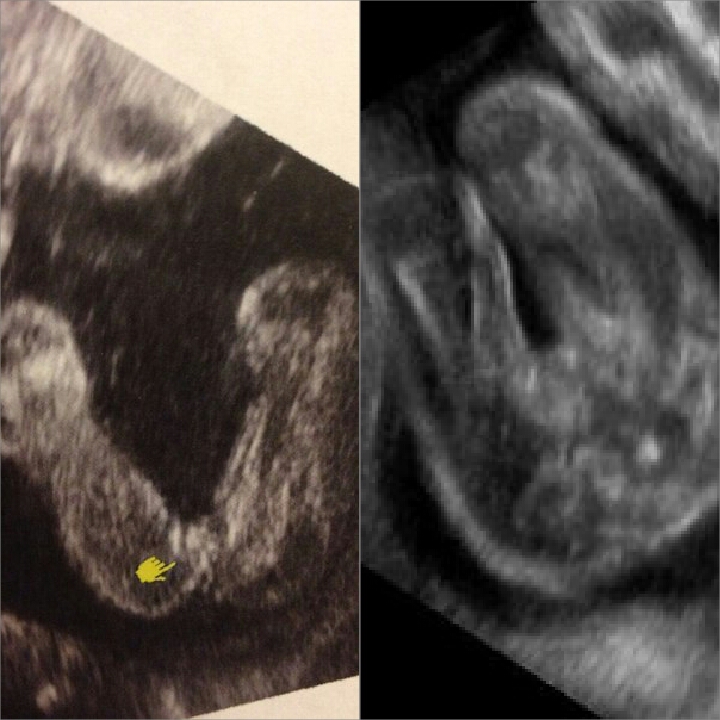

Слева - девочка, а справа мальчик (пенис зажат, но яички не спутаешь ни с чем), просто ноги поджал малыш.

Ракурсы не самые удачные)мне когда показывали то там всё было чётко и ясно,у сына такое внушительное хозяйство было,ни с чем не спутать,а у дочки сейчас всё так аккуратненько,прям персик))но если точно знать что разнополые,то мальчик справа,хотя там всё размыто и непонятно,слева девчушка однозначно!

На данных изображениях не вижу. Всегда когда видела писюн на узи он торчал прям оч сильно. Со всех ракурсов))))

Да я уж поняла. Но не очевидно. То ли ракурс совсем неудачный. У мальчиков обычно на таком сроке прям торчит

По мне, так две одинаковые попы.

Делая скидку на позу, хотелось бы, конечно, чтобы справа девочка была)))